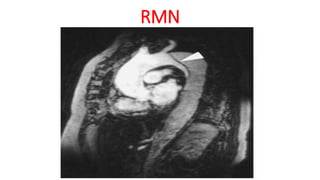

RMN